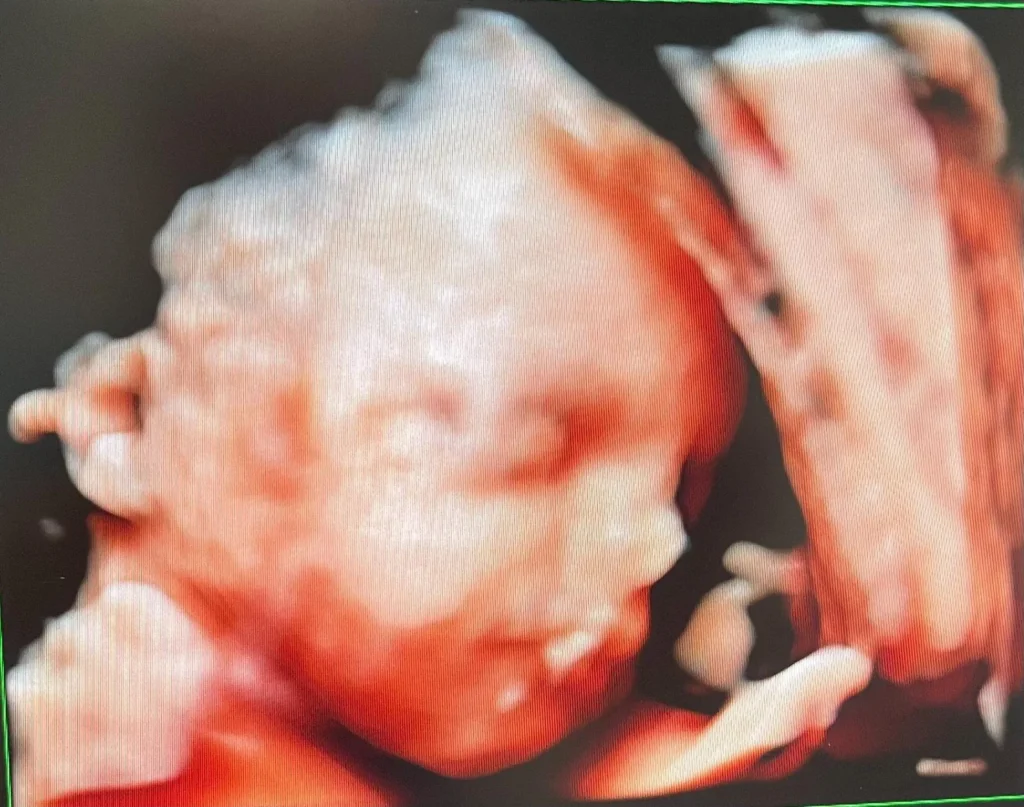

Hos Mors Mave i Aalborg tilbyder vi 3D/4D-scanning til dig, der ønsker at se dit barn helt tydeligt – i både bevægelse og udtryk.

Under scanningen får du lov at se, hvordan barnet bevæger sig, og vi tager billeder i høj opløsning, som du får med hjem.

En 3D/4D-scanning er en smuk og følelsesladet oplevelse, der ofte gør graviditeten endnu mere virkelig – både for jer og for eventuelle søskende.

Det bedste resultat opnås mellem uge 28 og 34, hvor barnet er udviklet, men stadig har god plads til bevægelse.

Hos Mors Mave bruger vi den nyeste Voluson S10 Expert BT22 fra GE, som giver billeder i topklasse.

Du får både et printet 3D-billede og digitale billeder sendt på mail efter scanningen.